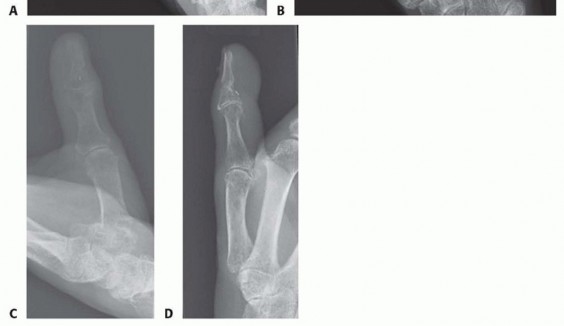

A survival rate greater than 80% is expected for replantation surgery.Functional outcomes are greatest for replantation of the thumb, proximal hand, and single digit distal to the FDS insertion (FIG 6A-D).5,6,13,16Recovery of sensation is correlated with function. As in other peripheral nerve injuries, age is the most important factor for recovery, with better results in younger patients. The average two-point discrimination inreplanted thumbs is 11 mm and in fingers is 8 mm.4 These values represent the average recovery for sharp amputation. Crush and avulsion mechanisms result in poorer two-point discrimination.Range of motion is related to level of amputation. Active PIP joint motion in replantations proximal to the FDS insertion average 35 degrees, whereas replantations distal to the FDS insertion result in 82 degrees of PIPjoint motion (FIG 6E-G).7

FIG 6 • A-D. This patient sustained an amputated thumb, which was successfully replanted with good cosmetic and functional results. E-G. Successful replantation of the ring and small fingers resulted in a functional hand capable of holding common objects. Vigilant reexamination of color, warmth, turgor, and capillary refill is necessary to decide whether exploration in the operating room is indicated. Revisions after 4 to 6 hours of reduced perfusionseldom result in digit salvage.7If venous engorgement occurs postoperatively, elevate the hand and remove constrictive dressings (including sutures that are too tight).Consideration for return to the operating room is based on intraoperative findings affecting the possibility of revising the venous anastomosis.If this is not possible, leeches or nail removal are used to alleviate venous congestion. These methods typically are used to bridge the first 4 to 6 days until adequate outflow is established.